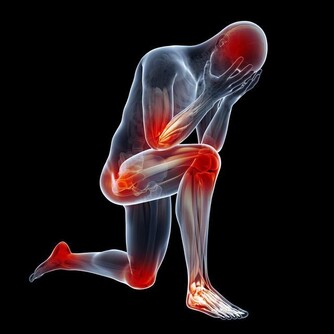

兒童一旦近視,度數就會持續增加,近視的眼軸像吹氣球般越吹越長,到成年才會停止。眼軸越拉長,眼睛的組織就會越薄越脆弱,容易產生很多近視並發症。

事實是,失明人口中,高度近視已經高居失明的第二大原因。日本及中國大陸在這一兩年的研究結果顯示,高度近視的視網膜黃斑退化也已經是老年人失明的第二大原因。甚至在日本,年輕成年人單眼失明的第一大原因,就是高度近視造成的,所以近視當然可怕。

但近視的可怕之處也在於此:高度近視引起視網膜黃斑退化所導致的失明,就算是再高明的眼科醫生也愛莫能助。